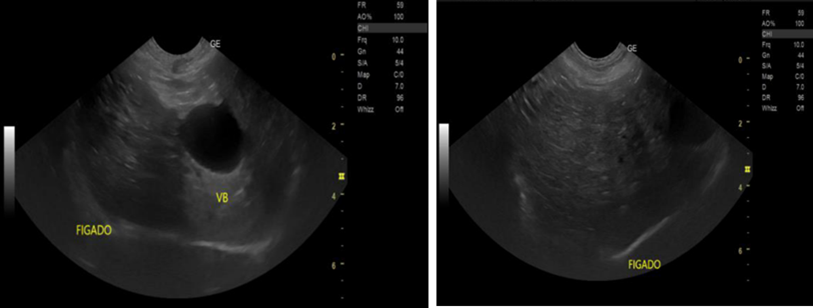

Primary Hepatic Leiomyosarcoma - A Rare Neoplasm with Diagnostic and Therapeutic Challenges

João Kleber de Almeida Gentile, Beatriz Terezinha Franco Renesto, Eloíza Helena Dias Quintela, Alexandre Sacchetti Bezerra, Flavia Magella, Luís Fernando Alves Miléo, Daniel de Castilho da Silva, Ronaldo Modesto de Souza Filho, André Cosme Oliveira

bjcr96